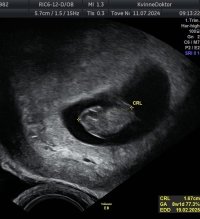

Tok du innvendig eller utvendig?Menstermin og ultralydtermin er begge 6+5. «Perfekt» hjerterytme, «perfekt» størrelsesforhold mellom embryo og plommesekk, ingen blødninger eller forstyrrende «flekker» på bildene og «perfekt» størrelse på embryoet etter «alder». Målt til 8,3 mm. Gynekologen sa at det nå er, basert på funnene, ca. 6% sannsynlighet for abort. Veldig hyggelig besøk hos Medicus før ferien!

Innvendig.Tok du innvendig eller utvendig?![]()